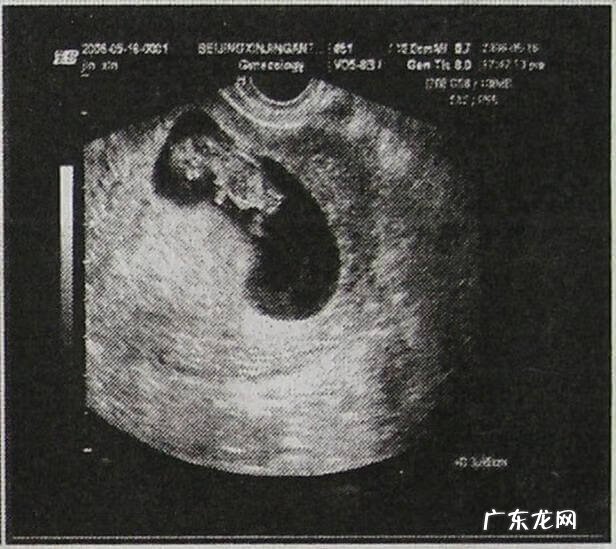

6周:胎儿长到0.85厘米,胎儿头部、脑泡、额面器官、呼吸、消化、神经等器官分化,B超胎囊清晰可见,并见胎芽及胎心跳 。

7周:胎儿长到1.33厘米,胚胎已具有人雏形,体节已全部分化,四肢分出,各系统进一步发育 。B超清楚看到胎芽及胎心跳,胎囊约占宫腔的l/3 。

8周:胎儿长到1.66厘米,胎形已定,可分出胎头、体及四肢,胎头大于躯干 。B超可见胎囊约占官腔1/2,胎儿形态及胎动清楚可见,并可看见卵黄囊 。

9周:胎儿长到2.15厘米,胎儿头大于胎体,各部表现更清晰,头颅开始钙化、胎盘开始发育 。B超可见胎囊几乎占满宫腔,胎儿轮廓更清晰,胎盘开始出现 。